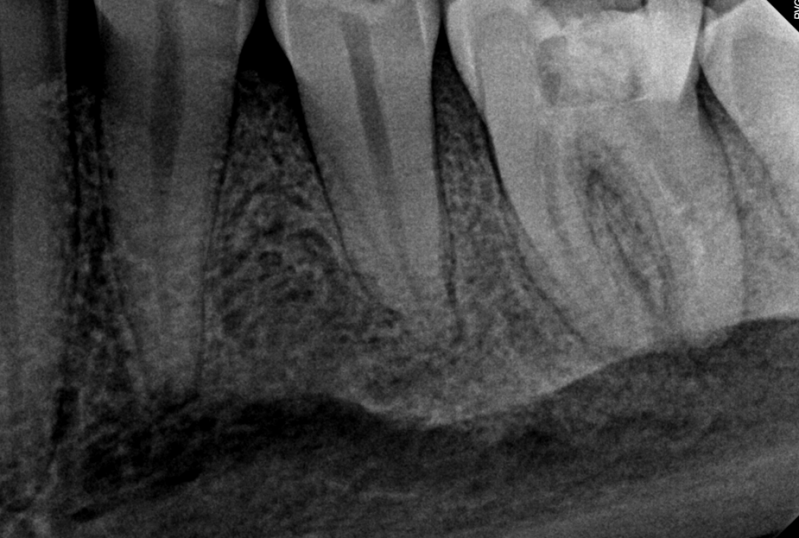

Case: RCT on Tooth #19

14-year-old male

Medical History: No significant findings (no medications, no allergies)

CC: None reported; referred due to radiographic findings on tooth #19

Dx: Pulp necrosis, Chronic apical abscess

Tx: Non-surgical root canal therapy (RCT) completed on tooth #19

Reflection

Locating the mesio-buccal canal presented a challenge due to calcification, requiring careful exploration and magnification. Additionally, a large periapical lesion was noted on the radiograph. The extent of the lesion highlights the importance of long-term follow-up to monitor healing and confirm resolution.